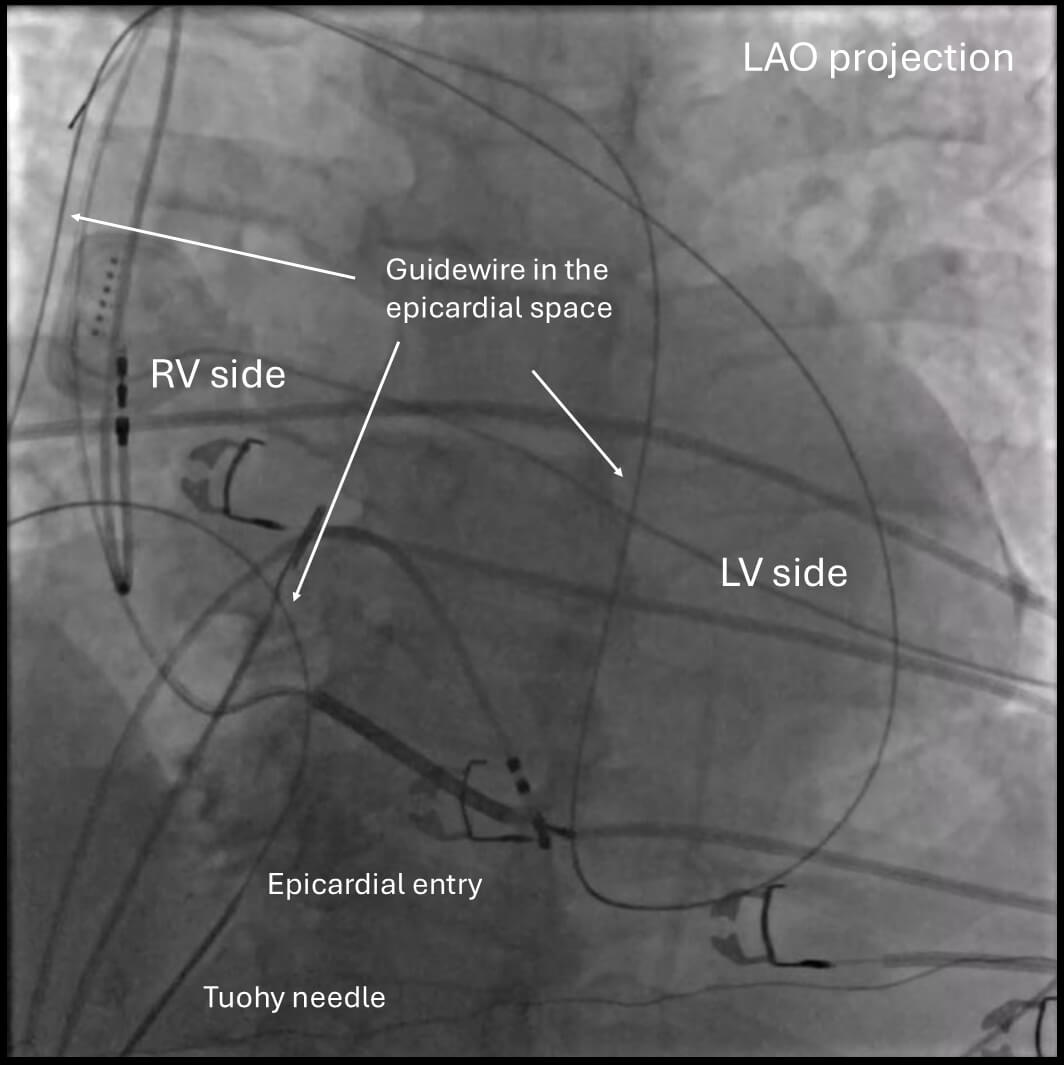

The puncture site is typically 1–2 cm inferior to the xiphoid process and slightly leftward. A skin incision is made to facilitate the passage of the large needle. While manually depressing the abdomen, the large-bore needle is advanced through the subcutaneous tissues and abdominal wall muscles toward the left shoulder, maintaining a shallow angle relative to the skin. Contrast was originally used only to confirm the needle placement once the needle is in the epicardial space. However, this was later modified to the use of contrast intermittently with fluoroscopic monitoring to observe a “tenting” of the parietal pericardium just before the puncture as well. Just before perforating the parietal pericardium, resistance may be felt as a “pulsatile feeling” from the needle. Once a “popping feeling” is felt, which indicates a puncture of the pericardium, contrast is injected to confirm the needle is in the intrapericardial space. A 0.035-inch guidewire is advanced under fluoroscopic visualization. It is important to confirm that the guidewire is not in the endocardium by fluoroscopy before sheath placement. Confirming the guidewire crossing from the right to the left side of the heart is strongly recommended using fluoroscopy with LAO projection (Fig. 2). One should also confirm that the wire is not outside the cardiac silhouette to make sure the wire is not in the pleural space. An intracardiac echocardiogram is also helpful to confirm that the guidewire is not in the RV. Following the wire placement, a long steerable or fixed sheath is inserted into the pericardial space. Anticoagulation is typically withheld until successful sheath placement to reduce the risk of hemorrhagic complications.

Fig. 2.

Confirmation of wire placement in the epicardial space. Confirming the guidewire crossing from the right side to the left side of the heart is generally recommended by fluoroscopy with an LAO projection. Note that the wire goes only within the cardiac silhouette. LAO, left anterior oblique; RV, right ventricle; LV, left ventricle.